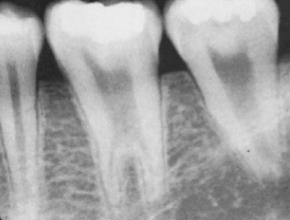

taurodontism

what is shown here?